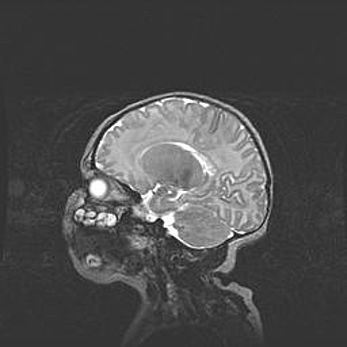

Наружная гидроцефалия с возможной атрофией височных областей.

Возраст: 28 дней

Вес: 3670 г

Пол: мужской

Окружность головы: 38 см

Срок гестации: 40 недель

Гидроцефалия головного мозга у новорожденных – это заболевание, которое характеризуется скоплением избыточного количества спинномозговой жидкости в желудочковой системе головного мозга в результате затруднения её перемещения от места выработки к месту поглощения в кровеносную систему или вследствие нарушения абсорбции. При открытой наружной форме гидроцефалии у новорожденных расширяются и переполняются субарахноидные пространства.

При нормотензивных  формах,  которые,  как  правило,  являются  следствием  перенесенных ишемических  повреждений  паренхимы  мозга,  возможно  сочетание микроцефалии  с нормотензивной гидроцефалией. В основе данных изменений лежит атрофия больших полушарий с преимущественной  локализацией  в  лобно-височных  областях.